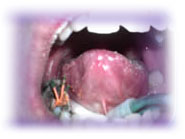

The dental cavity (caries) is one of the most widely spread diseases of human species. The caries is caused by certain types of acid-producing bacteria which are fed with the remains of the food left in the mouth. The most suitable medium for the multiplication of the bacteria in the mouth are various carbohydrates and sugars. As a result of disintegration of the food in the mouth, the Ph value in the mouth decreases. The acids from the mouth demineralize the tooth enamel and at this point the way for the bacteria is open to begin to feed themselves with the organic components of the teeth until the pulp begins to necrotize and then the process continues in the bone structures beneath the tooth. This process ends with the complete deterioration of the tooth structure. The granuloma or the cyst are created in the bone under the tooth and in the end the edema and the tooth extraction are inevitable.

It is very important that the caries is healed in the initial faze when the whole process can be stopped with the relatively small intervention by a filling. In case the dental pulp is damaged, the acute inflammatory process begins which is followed by severe pains. In that faze, the tooth can still be saved by an extraction of the dental pulp and the obturation of the root canal. If the process is chronic the pain will be low in intensity or it won't be felt at all and the most of the patients won't go to the dentist at this point. In that case, the dental pulp necrotize and the process continues in the bone structures. Then the granuloma or cyst appears in the bone structures under the tooth which is the defensive mechanism of the organism to the presence of the bacteria and the infection. It is rare that in this faze the tooth can be healed by using the conservative methods and more often the surgical intervention is needed. Very often the process is so advanced that that the bone structures are destroyed to the point where the tooth can not be saved and the extraction is inevitable.